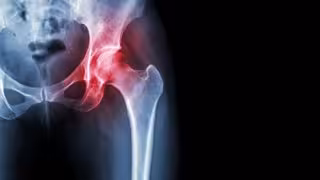

Necrosis avascular de cadera

"La fractura por fragilidad tiene un gran impacto en la calidad de vida de las personas", ha explicado el jefe del Servicio de Cirugía Ortopédica y Traumatología en el Hospital Universitario Infanta Leonor de Madrid, Ricardo Larraínzar, quien ha incidido en las cifras de mortalidad asociadas a la fractura de cadera: cinco por ciento en ingreso hospitalario, 33 por ciento en el primer año después de la fractura y hasta el 50 por ciento a los tres años.

También ha puesto de relieve las cifras de discapacidad motora derivada, así como ha avisado de que dos de cada 10 pacientes que se rompen la cadera no vuelven a comer solos. "Uno puede entender el déficit motor asociado a la fractura, pero, ¿comer solos? No ser capaz de alimentarse por sí solo es una muestra clara del impacto funcional que tiene este evento", ha expuesto.

Además, ha advertido de que tras una fractura de cadera existe una incidencia del 5 al 10 por ciento de fractura de la otra cadera, y de que un 70 por ciento de los pacientes con fractura de cadera presentan fractura vertebral previa, que en muchos casos pasó desapercibida.